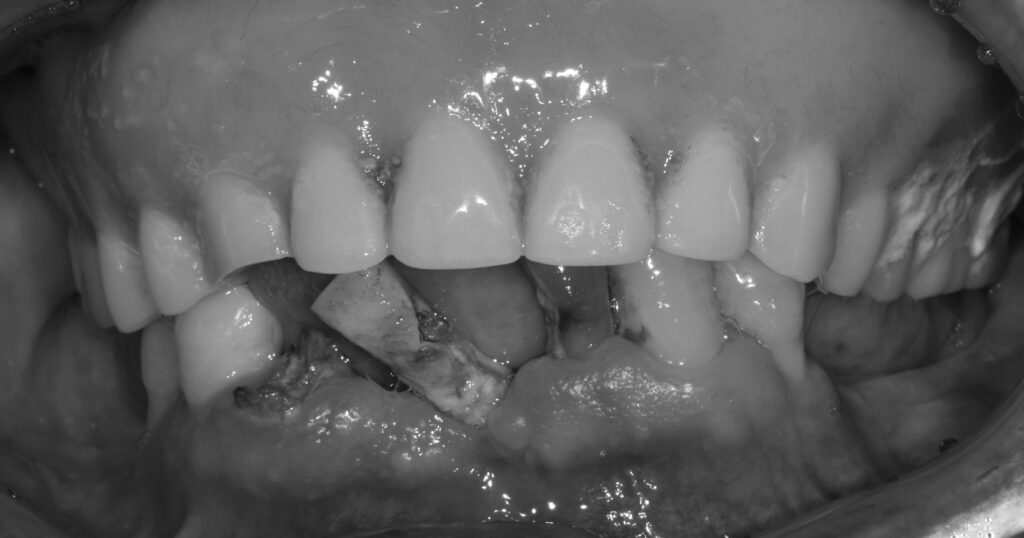

이분은 내원 당시 상악(위턱)에는 뿌리만 남은 치아들 위로 전체 틀니를 사용하고 계셨습니다.

하악(아래턱)의 경우에는 치아가 일부 남아 있었지만, 심한 치주염으로 인해 치아 대부분이 손상된 상태였습니다.

위턱에는 불편한 틀니를 쓰고 계셨고, 아래 치아들은 심한 염증으로 고통스러운 하루하루를 지내시다가 큰맘 먹고 내원하셨다고 하십니다.

수술 및 보철 과정까지 완료

임플란트 수술과 보철까지 완료된 모습입니다.